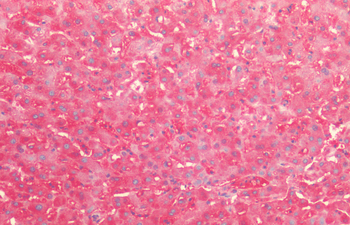

Immunohistochemistry analysis using Mouse Anti-Hsp60 Monoclonal Antibody, Clone LK-1. Tissue: colon carcinoma. Species: Human. Fixation: Formalin. Primary Antibody: Mouse Anti-Hsp60 Monoclonal Antibody at 1:100000 for 12 hours at 4°C. Secondary Antibody: Biotin Goat Anti-Mouse at 1:2000 for 1 hour at RT. Counterstain: Mayer Hematoxylin (purple/blue) nuclear stain at 200 μl for 2 minutes at RT. Localization: Inflammatory cells. Magnification: 40x.